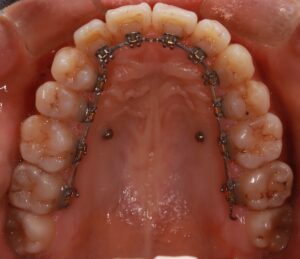

今回も上の歯に変化はありません。